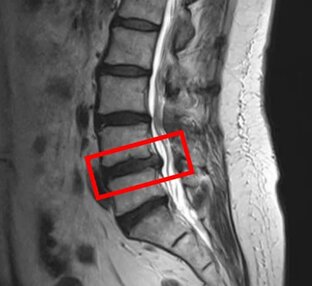

С согласия пациентов публикуем их истории. Пациент – женщина, 72 года Лечение в апреле 2024 года. Боли в пояснице появились в 2022 году. Была у разных врачей, принимала обезболивающие препараты, но улучшений не было. Трудно ходить. Хожу только с тростью. По данным МРТ и результатам осмотра пациентки выявлен стеноз позвоночного канала L4/L5, спондилолистез позвонков L4 и L5. Симптомы по 10-балльной шкале (0 – отсутствие симптомов, 10 – сильные боли/онемение): – боли в пояснице: 7; – боли в ногах: 9; – онемение в ногах: 9; – боли в ягодицах: 6...

С согласия пациентов публикуем их истории. Пациент – мужчина, 58 лет Лечение в апреле 2024 года. После 30 лет периодически повторялись приступы резких болей в пояснице (2–3 раза в год). В феврале после занятий с физиотерапевтом появилось онемение в левой ноге. По данным МРТ и результатам осмотра пациента выявлена межпозвоночная грыжа диска L4/L5, дегенерация межпозвоночных дисков L2/L3, L3/L4 и L5/S1. Симптомы по 10-балльной шкале (0 – отсутствие симптомов, 10 – сильные боли/онемение): – боли в пояснице: 3; – боли в ногах: 1; – онемение в ногах: 2; – боли в ягодицах: 2...

С согласия пациентов публикуем их истории. Пациент – мужчина, 48 лет Лечение в апреле 2024 года. Осенью 2023 года появились боли в правой ноге. В ближайшей больнице был поставлен диагноз “межпозвоночная грыжа”. Принимал обезболивающие препараты, ходил на физиотерапию. Симптомы в основном с правой стороны: боли в пояснице, боли в ягодице и правой ноге. При ходьбе болевые ощущения усиливаются. По данным МРТ и результатам осмотра пациента выявлена дегенерация межпозвоночных дисков L2/L3 и L5/S1, а также стеноз межпозвонковых отверстий L5/S1...

С согласия пациентов публикуем их истории. Пациент – мужчина, 73 года Лечение в марте 2024 года. История болезни В 2016 году появились боли в пояснице. Был поставлен диагноз “стеноз позвоночного канала, смещение позвонка”. Принимал обезболивающие препараты. В январе 2024 года боли усилились, появились судороги. Не могу долго ходить. Диагностика и лечение в клинике По данным МРТ и результатам осмотра пациента выявлен стеноз позвоночного канала L4/L5, а также дегенерация межпозвоночных дисков L3/L4, L5/S1...

С согласия пациентов публикуем их истории. Пациент – мужчина, 51 год Лечение в марте 2024 года. В студенческие годы играл в бейсбол. Иногда болела спина, но особо не обращал внимания. В 2022 году появились сильные боли в пояснице. Была диагностирована межпозвоночная грыжа. Ставил блокады, но особых улучшений не было. По данным МРТ и результатам осмотра пациента выявлена дегенерация и грыжа межпозвоночных дисков L4/L5, L5/S1. Симптомы по 10-балльной шкале (0 – отсутствие симптомов, 10 – сильные боли/онемение): – боли в пояснице: 8; – боли в ногах: 7; – онемение в ногах: 7; – боли в ягодицах: 7...